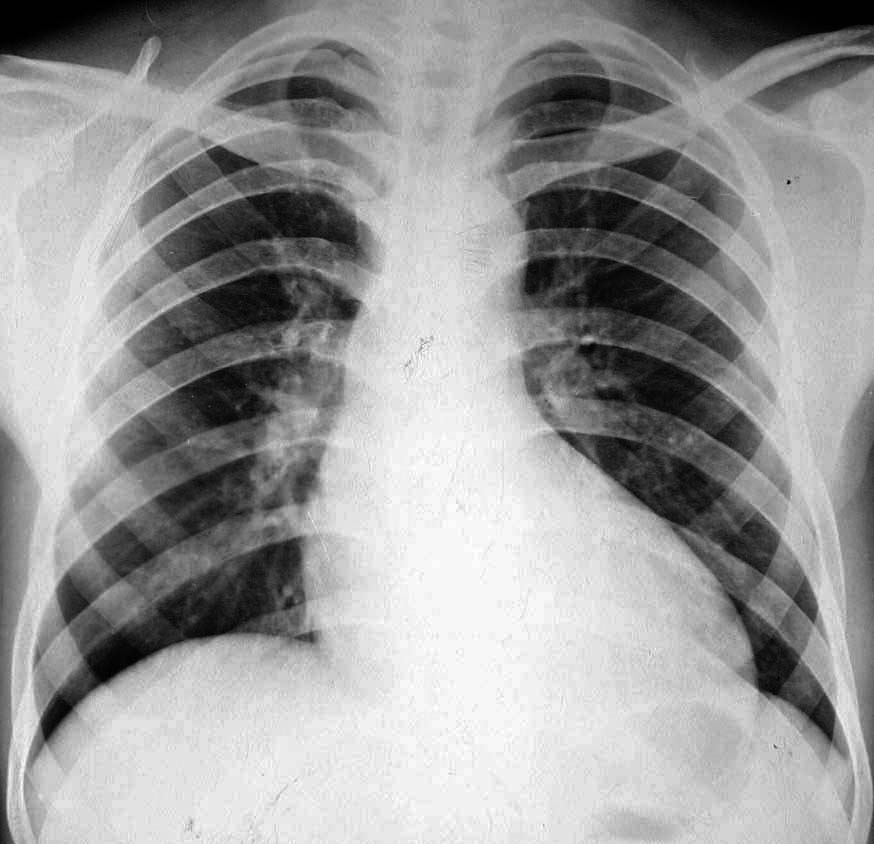

标题: X5497:风心病

升主动脉增宽,左心室增大,

主动脉型心,请结合临床。不支持风心病。

左室稍大,主动脉结增宽不明显,风心病所致单一主动脉瓣病变少,不太支持。

“主动脉型”心影,不排除法四可能;请结合临床及心脏超声检查。

主动脉增宽不明显,左心室增大,风心病可能不大,请提供临床资料。